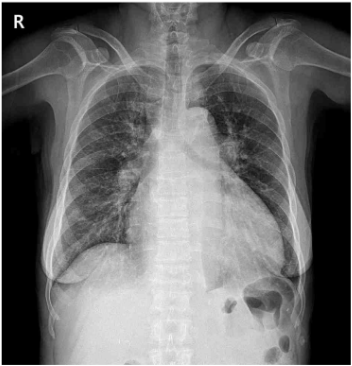

67세 여자가 1일 전부터 가슴이 칼로 찌르는 듯이 아파서 응급실에 왔다. 고혈압과 만성신부전으로 약물을 복용 중이며, 혈액투석은 아직 받지 않는다. 혈압 220/95 mmHg, 맥박 95회/분, 호흡 20회/분, 체온 36.7℃이다. 호흡음과 심음은 정상이다. 검사 결과는 다음과 같다. 심전도 사진, 가슴 X선사진 및 가슴 컴퓨터단층촬영 사진이다. 진단은?

CXR: Cardiomegaly, mediastinal widening

• 흉통은 가슴이 칼로 찌르는 듯한 양상이며 과거력으로 고혈압이 있으며 CXR에서 mediastinal widening이 관찰되므로 AD를 의심해야 한다.

CXR: Mediastinal widening